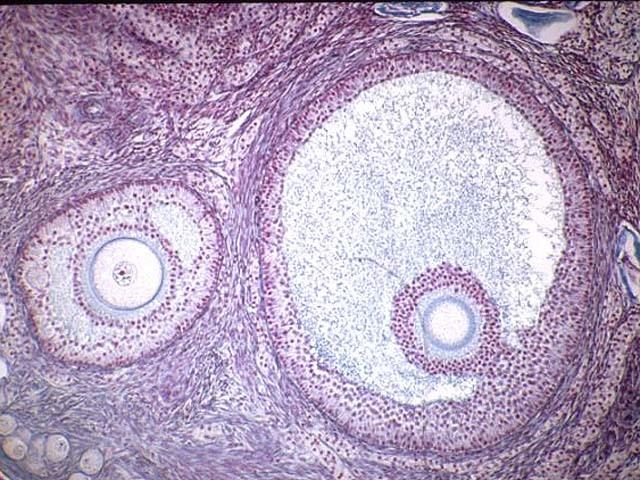

identify the histology slide

antrum

progesterone level in a normal uterine cycle

the ovary

primary follicle

theca folliculi

primary oocyte

zona pellucida

antrum

secondary oocyte

corpus luteum